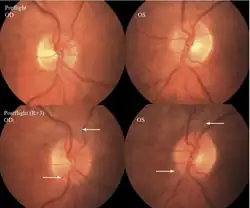

The first U.S. case of visual changes observed on orbit was reported by a long-duration astronaut that noticed a marked decrease in near-visual acuity throughout his mission on board the ISS, but at no time reported headaches, transient visual obscurations, pulsatile tinnitus or diplopia (double vision). His postflight fundus examination (Figure 1) revealed choroidal folds below the optic disc and a single cotton-wool spot in the inferior arcade of the right eye. The acquired choroidal folds gradually improved, but were still present 3 year postflight. The left eye examination was normal. There was no documented evidence of optic-disc edema in either eye. Brain MRI, lumbar puncture, and OCT were not performed preflight or postflight on this astronaut.[5]

Figure 1:Fundus examination of the first case of visual changes from long-duration spaceflight. Fundus examination revealed choroidal folds inferior to the optic disc and a single cotton-wool spot in the inferior arcade of the right eye (white arrow).

The second case of visual changes during long-duration spaceflight on board the ISS was reported approximately 3 months after launch when the astronaut noticed that he could now only see Earth clearly while looking through his reading glasses. The change continued for the remainder of the mission without noticeable improvement or progression. He did not complain of transient visual obscurations, headaches, diplopia, pulsatile tinnitus or visual changes during eye movement. In the months since landing, he has noticed a gradual, but incomplete, improvement in vision.[5]

Figure 2: Fundus examination of second case of visual changes from long-duration spaceflight. Fundoscopic images showing choroidal folds (white arrows) in the papillomacular bundle area in the right eye and left eye and a cotton-wool spot (bottom arrow) at the inferior arcade in the left eye. Both optic discs show grade 1 disc edema.

Figure 13: Fundus examination of the sixth case of visual changes from long-duration spaceflight. Preflight images of normal optic disc. Postflight right and left optic disc showing grade 1 (superior and nasal) edema at the right optic disc.

The seventh case of visual changes associated with spaceflight is significant in that it was eventually treated postflight. Approximately 2 months into the ISS mission, the astronaut reported a progressive decrease in his near and far acuity in both eyes. The ISS cabin pressure, CO2 and O2 levels were reported to be within normal operating limits and the astronaut was not exposed to any toxic substances. He never experienced losses in subjective best-corrected acuity, color vision or stereopsis. A fundus examination revealed a grade 1 bilateral optic-disc edema and choroidal folds (Figure 15).[5]

Figure 15: Preflight images of the right and left optic discs (upper). Postflight images of the ONH showing in more detail the extent of the edematous optic-disc margins and glutting of the superior and inferior nerve fiber layer axons OD and OS (arrows) (lower).